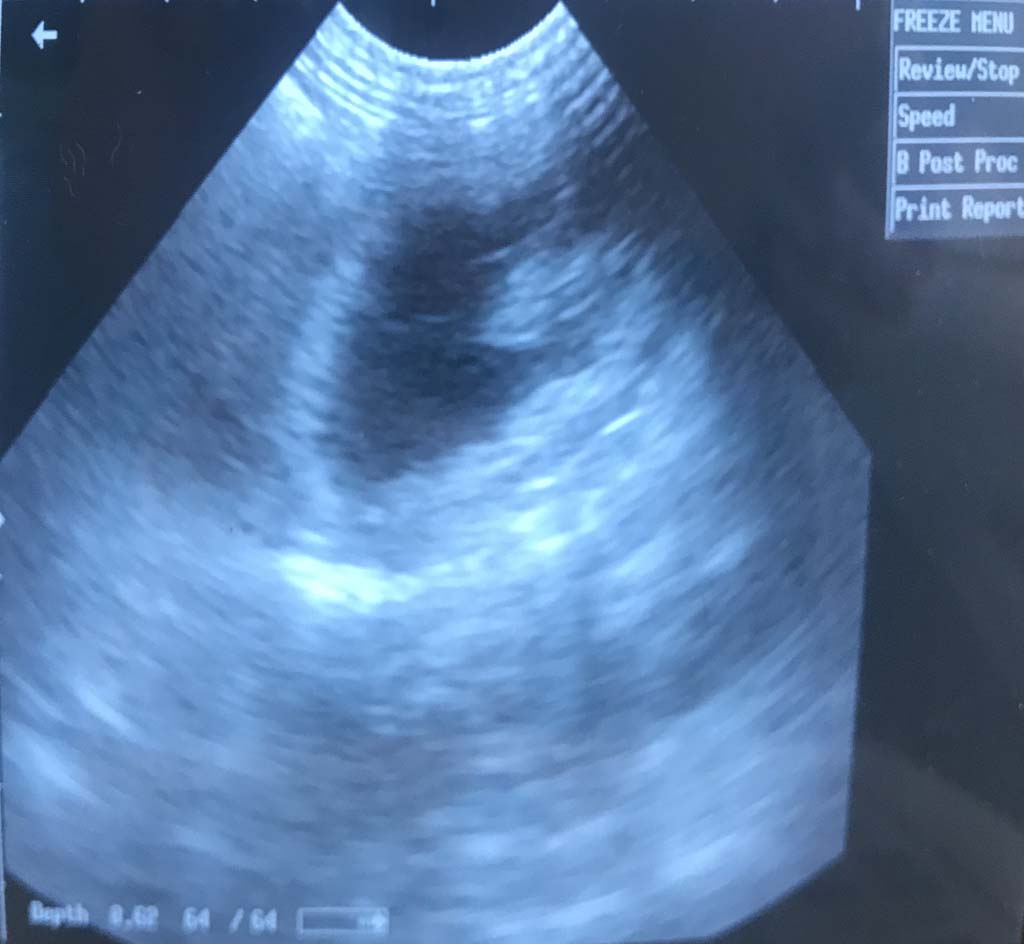

Am Tag 55 (29.01.2018) haben wir dann endlich mal nachgeschaut

Was wir sehen können ..... einige haben mal wieder die Beinchen nach hinten und so werden sie wohl auch mit diesen zuerst auf die Welt kommen. Wir denken nicht, dass sie sich noch drehen, da es dafür inzwischen zu eng bei Mama ist. Das ist soweit aber auch nicht unüblich bei Hundegeburten und so hoffen wir, dass das alles gut klappt. Was wir aber auch sehen können, ist die Anzahl Welpen :-). Diese verraten wir hier an dieser Stelle nicht, da wir euch ja auch noch ein wenig Spannung bereiten möchten, bevor es dann losgeht. Was wir nicht sehen können .... die Farben ... dies ist uns aber zum aktuellen Zeitpunkt auch nicht so wichtig, da wir uns erst einmal eine reibungslose Geburt für Mama Chili mit gesunden Welpen wünschen.

Viele Termine standen an, und so waren wir etwas später als sonst beim Ultraschall mit unserer Chili.

Aber es hat sich gelohnt. Chili ist heute an Tag 31 der Trächtigkeit für tragend befunden worden. Somit freuen wir uns riesig auf unseren P-Wurf. Auch sind wir uns sicher, dass dies einige mehr tun, da sie bereits auf diesen Wurf gewartet und mit uns gefiebert haben.